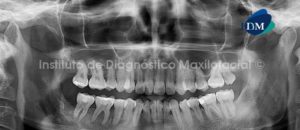

Paciente de sexo femenino y de 38 años de edad, es referida al Instituto de Diagnóstico Maxilofacial para la evaluación de un proceso infeccioso en el lado derecho del maxilar inferior.